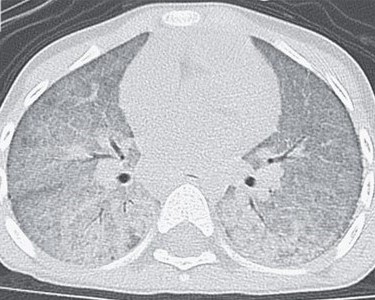

You are rotating on the pediatric wards and are asked to make a diagnosis in a 3-year-old

girl who was admitted because of recurrent fevers and progressive shortness of breath.

Examination of her lungs reveals diffuse inspiratory crackles and signs of patchy

consolidations bilaterally. Her hemoglobin level is 5.3 mg per deciliter (reference

range 11.6 to 14.8). A CT scan of her chest is shown below. What is your diagnosis,

what test(s) would you order to confirm your diagnosis, and what treatment, if any,

do you recommend?

DIAGNOSIS: Idiopathic pulmonary hemosiderosis (IPH). IPH is a disorder of unknown

etiology that is characterized by recurrent pulmonary hemorrhage with the consequent

development of pulmonary fibrosis and iron deficiency anemia. Described postmortem

by Virchow in 1864 the first antemortem diagnosis of IPH was made by Waldenstrom in

1994. A rare disorder (0.24 to 1.23 cases/million) it is treated with immunosupressants

(glucocorticoids, hydroxychloroquine, azathioprine, cyclophosphamide). Hemosiderin

ladened macrophages are found on lung biopsy and in brochoaveolar lavage specimens

(see below).

Chest x-ray ishows diffuse pulmonary hemorrhage with elements of pulmonary fibosis.